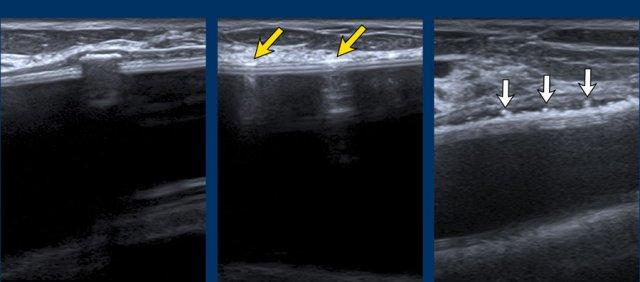

Dấu hiệu thang (Stepladder sign)

Siêu âm có thể phát hiện vỡ túi trong bao xơ bằng cách xác định một chuỗi các đường thẳng hoặc đường cong tăng âm nằm ngang, tương đối song song với nhau, đi ngang qua bên trong lòng túi độn, thường được gọi là “dấu hiệu thang” (stepladder sign).

Điều quan trọng là không được nhầm lẫn dấu hiệu thang với các nếp gấp hướng tâm nổi bật bình thường.

Thêm các ví dụ về “dấu hiệu thang”.

Ở bệnh nhân này, vôi hóa bao xơ nặng nề đã che khuất tình trạng của túi độn.

Tuy nhiên, khi quan sát từ một góc độ khác, dấu hiệu thang cho thấy rõ ràng có vỡ túi.

Do vôi hóa lan rộng, không thể xác định chắc chắn liệu đây chỉ là vỡ túi trong bao xơ hay còn kèm theo rò rỉ Silicone ngoài bao xơ.